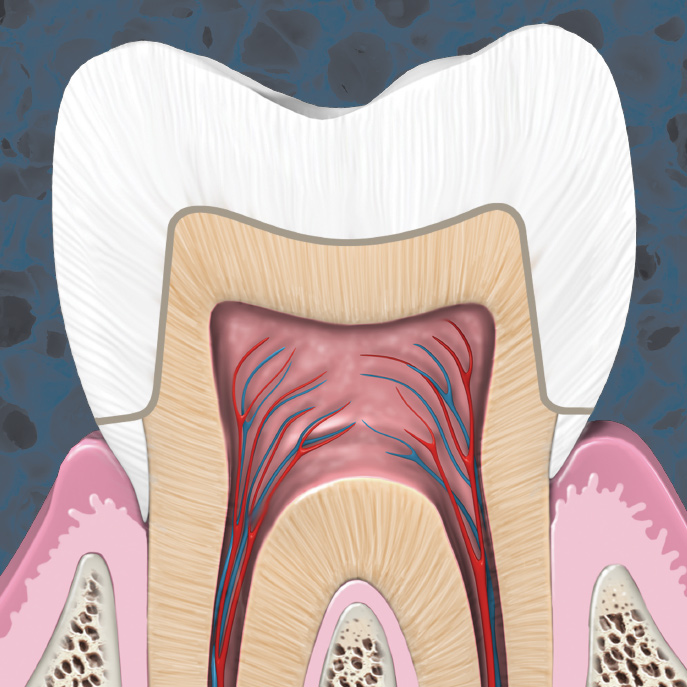

Steps to Endodontic Success for the General Practice

Stephen Christy, DMD

Wednesday, September 29, 2021

This Inside Dentistry eBook offers a continuing education (CE) article that serves as a step-by-step guide for general dentists to achieve endodontic success in their practices. Download to earn 2 FREE CEU now!

Biologic Approach To Endodontics with 3D Shaping

Monday, July 10, 2017

Endodontic treatment approaches have evolved to preserve natural tooth structure. 3D shaping technology is ushering in a new biologic approach in endodontic instrumentation. Learn how its unique design safely, efficiently, and effectively cleans the root canal system while respecting the canal anato...

Managing the Pulpal Response with High Performance Materials

Asle T. Klemma, DDS

Monday, October 3, 2016

Whether a restorative procedure is simple or complex, the pulpal health of the tooth is essential for long-term success and patient satisfaction. Learn about a new class of material that offers unique features for full pulpal protection.

The Management of Common Endodontic Emergencies

Tuesday, September 6, 2016

With many walk-in patients, general practices must be prepared to diagnose and treat a variety of moderately complicated endodontic emergencies. Learn how to develop an action plan for common emergencies, either to relieve the patient’s pain immediately or complete the endodontics definitively.